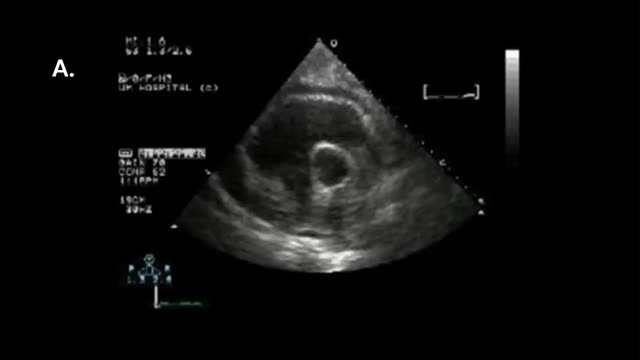

El postoperado de cirugía cardiaca (PC) presenta ciertas dificultades técnicas relacionadas con la limitación para la movilización del paciente: presencia de apósitos, drenajes, imposibilidad de utilizar la vía subxifoidea, dolor posquirúrgico, intubación, soporte ventilatorio, etc. (fig. 1). Son limitaciones técnicas que dificultan la adquisición de imágenes, que, junto con la presencia frecuente de coágulos loculados o de derrame pericárdico-pleural, podrían dificultar la interpretación del estudio ecográfico, precisando, en ocasiones, la combinación de otras técnicas para una adecuada evaluación.

Estudio pulmonarDadas las limitaciones anatómicas comentadas, parece práctico realizar un estudio modificado propuesto por Volpicelli3,4 (fig. 1A). Para completar la información sobre este apartado, se remite al lector a los capítulos 3 y 4 de esta serie.